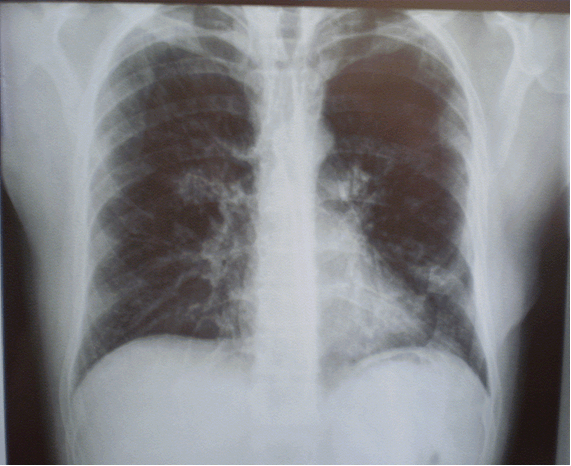

Клинический случай. Больной П., 32 лет, поступил в пульмонологическое отделение НУЗ «ЦКБ №1 ОАО «РЖД» в связи с выявлением при диспансерном обследовании изменений на флюорограмме в виде усиления и деформации легочного рисунка в прикорневых областях обоих легких. Амбулаторно была проведена рентгенография органов грудной клетки, на которой вышеуказанные изменения были подтверждены (рис. 1). Для дообследования и верификации диагноза направлен в стационар.

Рисунок 1. Рентгенограмма органов грудной клетки больного П.: легочный рисунок диффузно усилен и деформирован на всем протяжении за счет интерстициального компонента